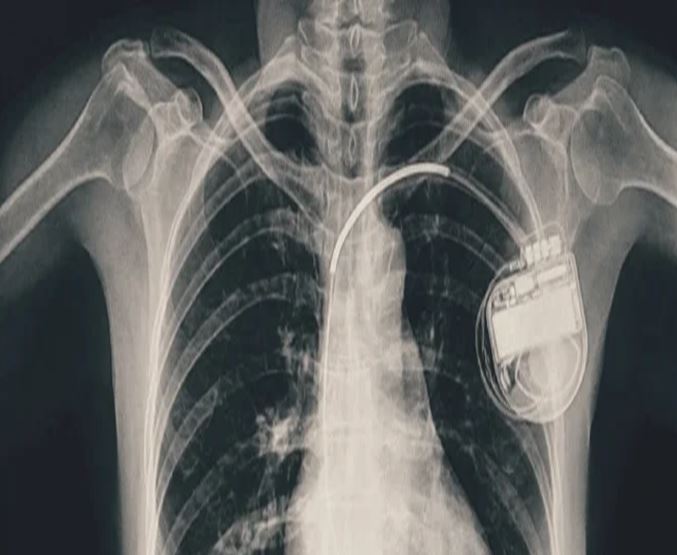

भोपाल। भोपाल मेमोरियल अस्पताल एवं अनुसंधान केंद्र (बीएमएचआरसी) के कार्डियोलॉजी विभाग ने एक दुर्लभ और चुनौतीपूर्ण चिकित्सा उपलब्धि हासिल की है। यहां 13 वर्ष की गैस पीड़ित आश्रित बालिका को इमरजेंसी में डुअल चेंबर पेसमेकर लगाकर उसकी जान बचाई गई। अब बालिका की हालत बेहतर है और उसे अस्पताल से छुट्टी दे दी गई है। यह प्रक्रिया सहायक प्रोफेसर डॉ. अमन चतुर्वेदी और उनकी टीम द्वारा सफलतापूर्वक की गई।

तीन वर्ष की आयु में दिल में था छेद

पेसमेकर एक छोटा उपकरण होता है, जो दिल की धड़कन को नियंत्रित करता है। यह दिल को सही गति से धड़कने में मदद करता है। सिंगल चेंबर पेसमेकर हार्ट के सिर्फ एक चेंबर को इलैक्ट्रिक सिग्नल देता है, जबकि डुअल चेंबर पेसमेकर दिल के दो भागों-ऊपरी (एट्रियम) और निचले (वेन्ट्रिकल) चेंबरों को दोनों को सिग्नल भेजता है, जिससे दिल की धड़कन और भी प्राकृतिक तरीके से चलती है। बच्ची के मामले में डुअल चेंबर पेसमेकर इसलिए लगाया गया क्योंकि उसकी स्थिति अधिक जटिल थी और बेहतर तालमेल के लिए दोनों चेंबर तक एकसाथ सिग्नल देना ज़रूरी था।